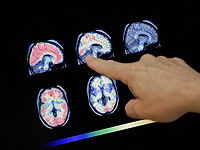

Модель сканирования мозга на основе ИИ распознает инсульт, опухоли мозга и аневризмы

Ученые из Королевского колледжа Лондона провели исследование, опубликованное в журнале Radiology AI, которое демонстрирует, как искусственный интеллект может помочь справиться с увеличивающимися задержками в радиологии. Эти задержки вызваны нехваткой специалистов и постоянным ростом количества назначаемых МРТ-исследований уже более десяти лет.

Подобные проволочки нередко замедляют начало лечения и могут ухудшать прогноз для пациентов, поскольку МРТ играет ключевую роль в выявлении и наблюдении множества заболеваний мозга, включая инсульты, опухоли и аневризмы. ИИ способен уменьшить нагрузку на радиологические отделения, автоматически сортируя снимки и ускоряя подготовку заключений.

Для проверки эффективности разработанную модель сначала научили определять, является ли скан нормальным или содержит патологию. Результаты оказались сопоставимыми с оценками опытных рентгенологов. Затем систему протестировали на выявлении конкретных заболеваний – инсульта, рассеянного склероза и опухолей мозга – используя новые МРТ-снимки, которые не входили в обучающий набор. Модель успешно справилась и с этой задачей.

Обычно ИИ обучают на больших наборах данных, которые вручную размечают специалисты, что требует значительных ресурсов. Чтобы избежать этих сложностей, исследователи создали модель, способную обучаться самостоятельно, используя более 60 000 имеющихся МРТ мозга вместе с соответствующими медицинскими заключениями. Ученые также настроили модель так, что она способна по загруженному МРТ-снимку или по текстовому запросу – например, "глиома" (разновидность опухоли мозга) – находить и показывать похожие случаи. Это может быть полезно как для уточнения диагноза, так и для обучения специалистов.

Результаты исследования демонстрируют, что модель можно применять прямо в процессе проведения МРТ: она способна обнаруживать аномалии в реальном времени и помогать врачам принимать решения. ИИ может подсказывать возможные находки, указывать на ошибки в заключениях или подбирать аналогичные случаи из архивов. Все это ускоряет диагностический процесс, сокращает время ожидания результатов и в конечном итоге улучшает качество лечения пациентов.